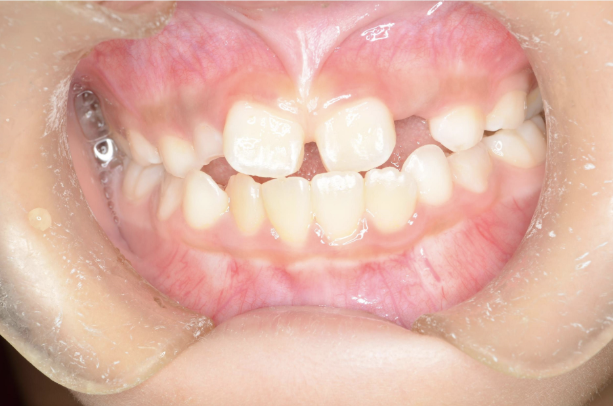

お子さんが「矯正治療」をはじめる時に直面する問題は 「装置が目立つ」、 そして「歯を抜く」ことがあげられます。

10歳を超えてからの治療開始ではそのようにならざるを得ないことが多いのです。

しかしながら、5〜7歳頃に治療をスタートすれば 目立ちにくい装置で、歯を抜かずに治療できることがあります。

また5〜7歳頃から治療を開始すると、骨格を改善することが可能です。

骨格が改善されるとお顔つきが良くなることが期待できます。

このように低年齢で矯正治療をスタートすることで得られるメリットがたくさんあります。

10歳を過ぎてからの矯正治療の場合、大人の歯を抜いて治療することが多くなります。 一方、下の前歯が生えてくる5〜7歳頃から治療を始めると、大人の歯を抜かずに治療することが可能です。 抜かずに治療するには早期に治療を開始することが大切です。

歯並びが悪いのは、あごの骨が成長不足で小さいことで起こります。 当院で行なっているこどもの歯ならび治療はあごの骨に働きかけることができます。 骨に働きかけることで成長不足のお子さんの骨が成長して、顔つきが良い方向に変わっていく可能性があります。 実は大きくなってからの矯正治療は歯が並んでいるだけで骨やお顔つきは変わっていないのです。 5〜7歳ぐらいで治療を開始すると成長不足の骨に働きかけて、より良い顔つきになれる可能性があります。